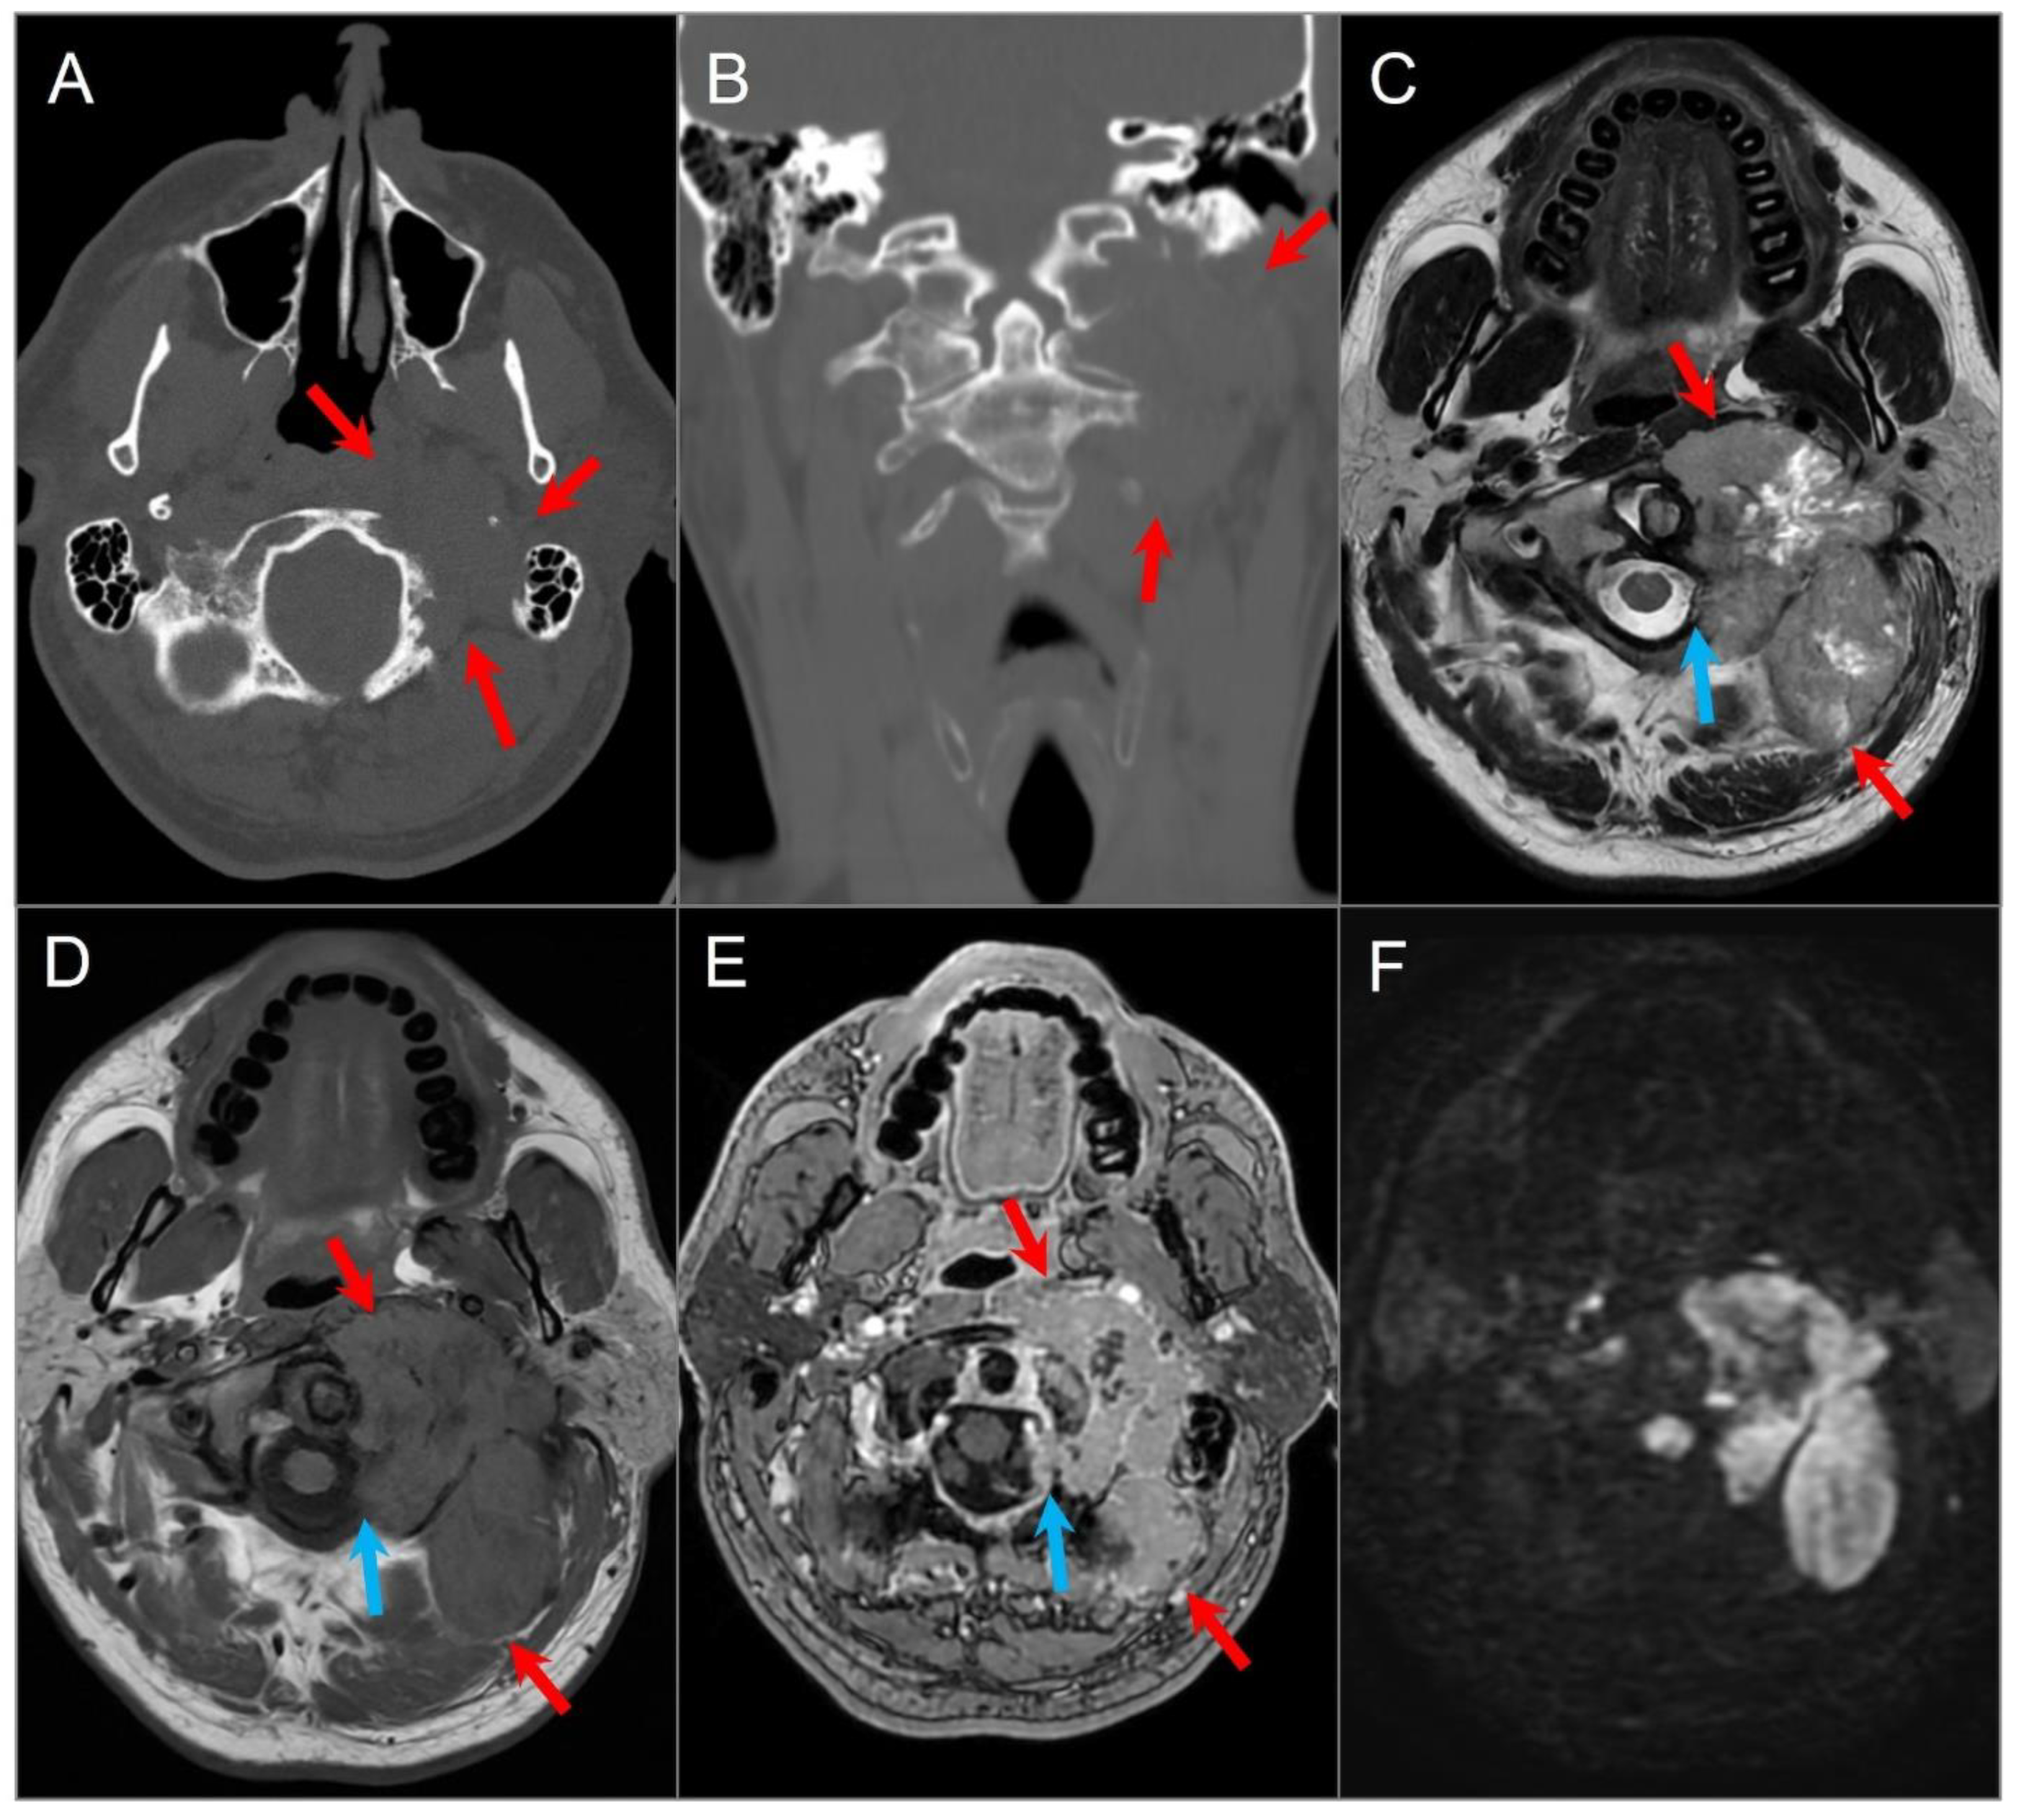

4.4.1. Chordoma

4.4.2. Chondrosarcoma